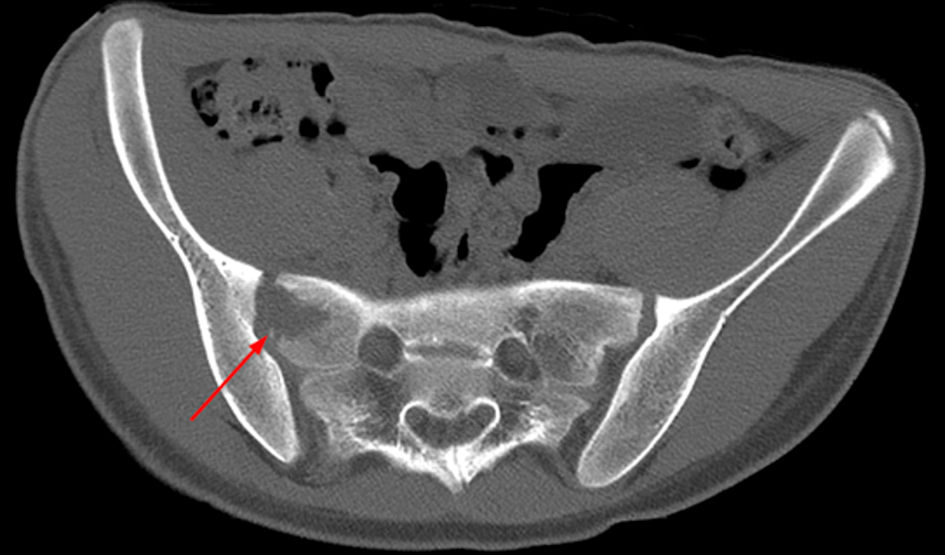

A CT scan of the pelvis was performed and showed an osteolytic lesion in the right sacrum. There was an asymmetry of the gluteal muscles where the soft tissues on the right side seemed enlarged (Fig. 3). A magnetic resonance imaging (MRI) scan was performed to rule out malignancy (Fig. 4). This showed edema in the right sacrum with a small fluid collection adjacent to the SI joint. An ultrasound of the abdomen was performed to exclude signs of gastrointestinal bacterial translocation, which was negative.

![]() Click for large image | Figure 3. Axial CT of the pelvis, bone setting, showing an osteolytic lesion in the right sacrum (arrow). CT: computed tomography. |